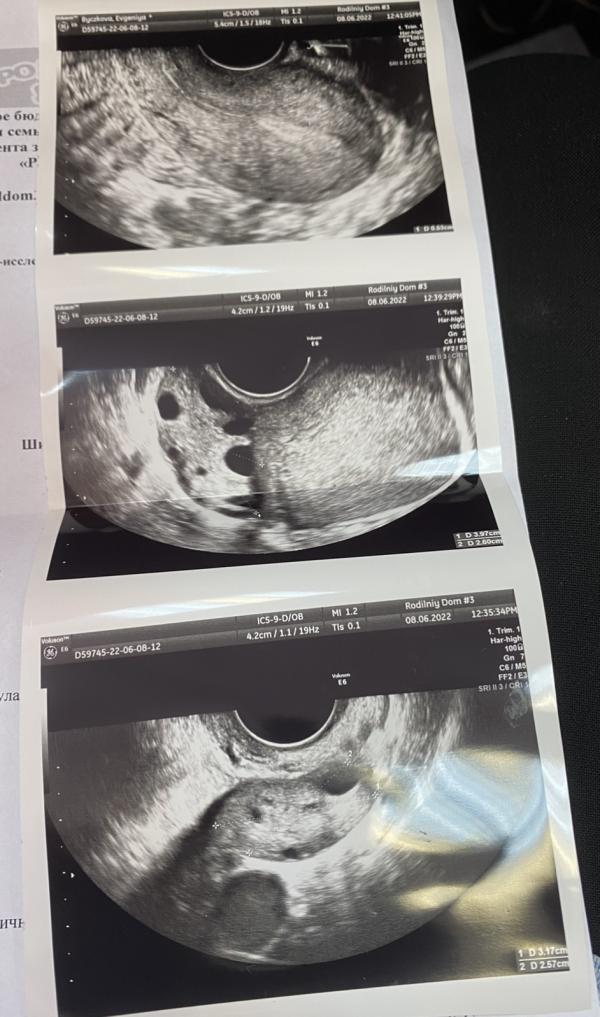

Была сегодня на узи, 7 дмц. Вроде все хорошо, а вроде и не понятно…. Нужно выяснить, происходит ли в итоге овуляция вообще.

Раньше все было прекрасно, сейчас каждый раз что-то новое вылазит. С 12 дц будем смотреть, что там происходит. Наделяюсь, что в итоге овуляция есть 🙌🏼